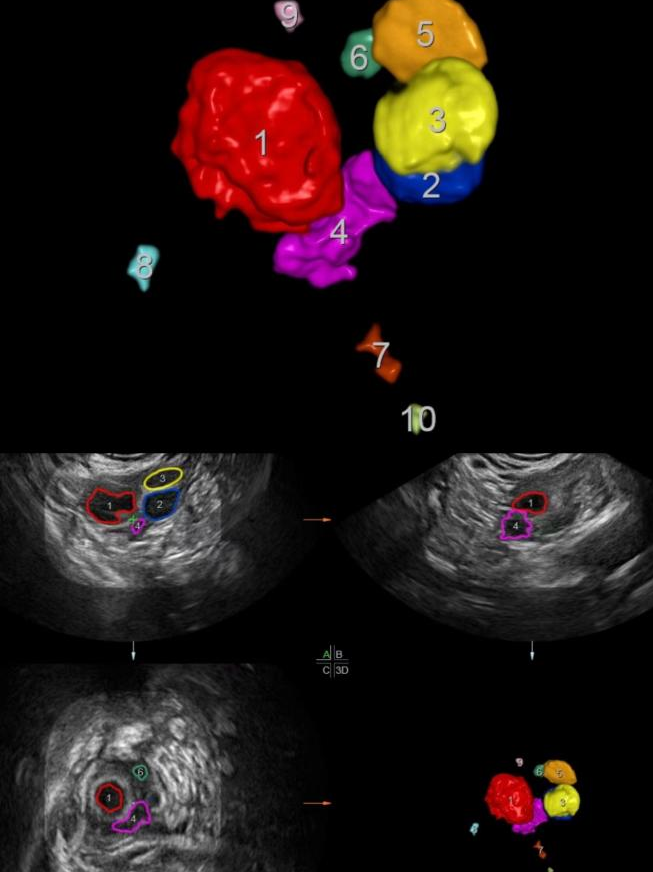

三维成像智能卵泡检测